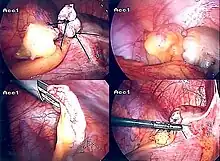

Laparoscopic appendectomy

Laparoscopic appendectomy was introduced in 1983 and has become an increasingly prevalent intervention for acute appendicitis.[96] This surgical procedure consists of making three to four incisions in the abdomen, each 0.25 to 0.5 inches (6.4 to 12.7 mm) long. This type of appendectomy is made by inserting a special surgical tool called a laparoscope into one of the incisions. The laparoscope is connected to a monitor outside the person's body, and it is designed to help the surgeon inspect the infected area in the abdomen. The other two incisions are made for the specific removal of the appendix by using surgical instruments. Laparoscopic surgery requires general anesthesia, and it can last up to two hours. Laparoscopic appendectomy has several advantages over open appendectomy, including a shorter post-operative recovery, less post-operative pain, and a lower superficial surgical site infection rate. However, the occurrence of an intra-abdominal abscess is almost three times more prevalent in laparoscopic appendectomy than open appendectomy.[97]